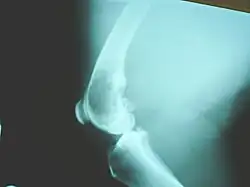

Diagnosis

X-rays is the initial imaging of choice to diagnose osteosarcoma. Some characteristics of osteosarcoma on X-rays are sunburst appearance and Codman triangle (elevation of bony cortex by the tumour that caused new bone formation). CT scan is helpful in defining the bony anatomy, the integrity of the bony cortex, detecting pathologic fracture, and assessing ossification (laying of new bone materials) and calcification of the cartilage. On the other hand, soft tissue and medullary cavity is better imaged by MRI scan.[23]

Osteosarcomas tend to occur at the sites of bone growth, presumably because proliferation makes osteoblastic cells in this region prone to acquire mutations that could lead to transformation of cells (the RB gene and p53 gene are commonly involved). The tumor may be localized at the end of the long bone (commonly in the metaphysis). Most often it affects the proximal end of tibia or humerus, or distal end of femur. Osteosarcoma tends to affect regions around the knee in 60% of cases, 15% around the hip, 10% at the shoulder, and 8% in the jaw. The tumor is solid, hard, irregular ("fir-tree," "moth-eaten", or "sun-burst" appearance on X-ray examination) due to the tumor spicules of calcified bone radiating at right angles. These right angles form what is known as a Codman triangle, which is characteristic but not diagnostic of osteosarcoma. Surrounding tissues are infiltrated.